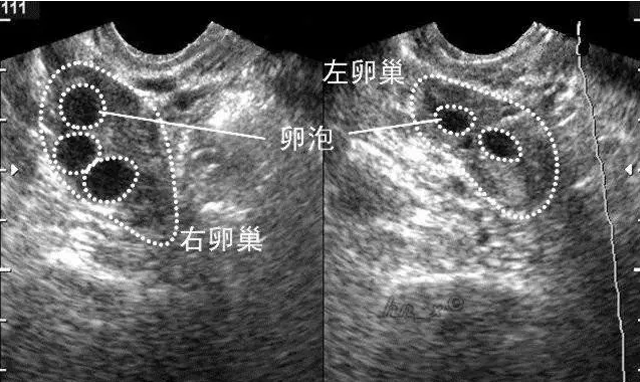

一般来说,试管婴儿都会打排卵针,因为试管婴儿毕竟不是百分百成功,所以每次取卵需要取出3-5枚卵细胞,正常排卵是不够的,所以需要打促卵针,刺激卵巢排出卵子,所以试管婴儿会增加卵巢癌风险。

而在人工取卵过程中中,痛苦的程度是最高的,这个过程需要用长长的取卵针刺破卵泡,针长的像是一根织毛线用的针,为了卵泡质量,有人选择不接受麻醉,就这样被一针一针戳进去,疼到冷汗直冒。